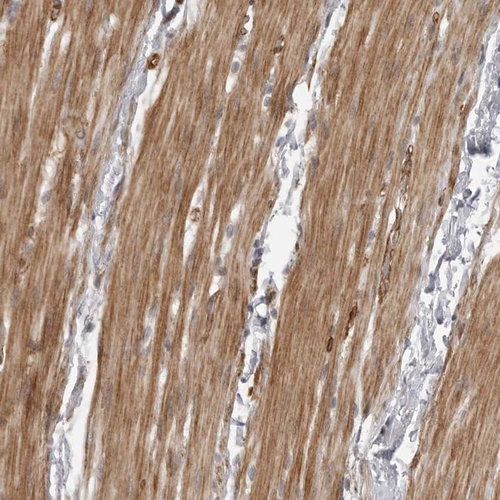

Immunohistochemical staining of human smooth muscle shows distinct cytoplasmic positivity.